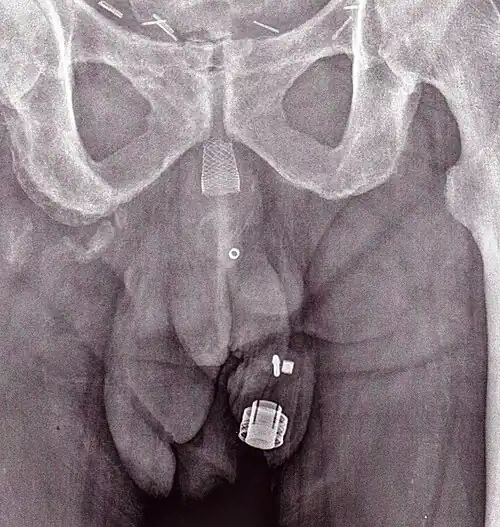

An X-ray image of implanted ZSI 375. The device is deactivated – the spring is compressed below the top of the cylinder. Patient is incontinent.

An X-ray image of implanted ZSI 375. The device is deactivated – the spring is compressed below the top of the cylinder. Patient is incontinent. -

An X-ray image of implanted ZSI 375. The device is activated – the spring is decompressed at the top of the cylinder. Patient is continent.

An X-ray image of implanted ZSI 375. The device is activated – the spring is decompressed at the top of the cylinder. Patient is continent. -